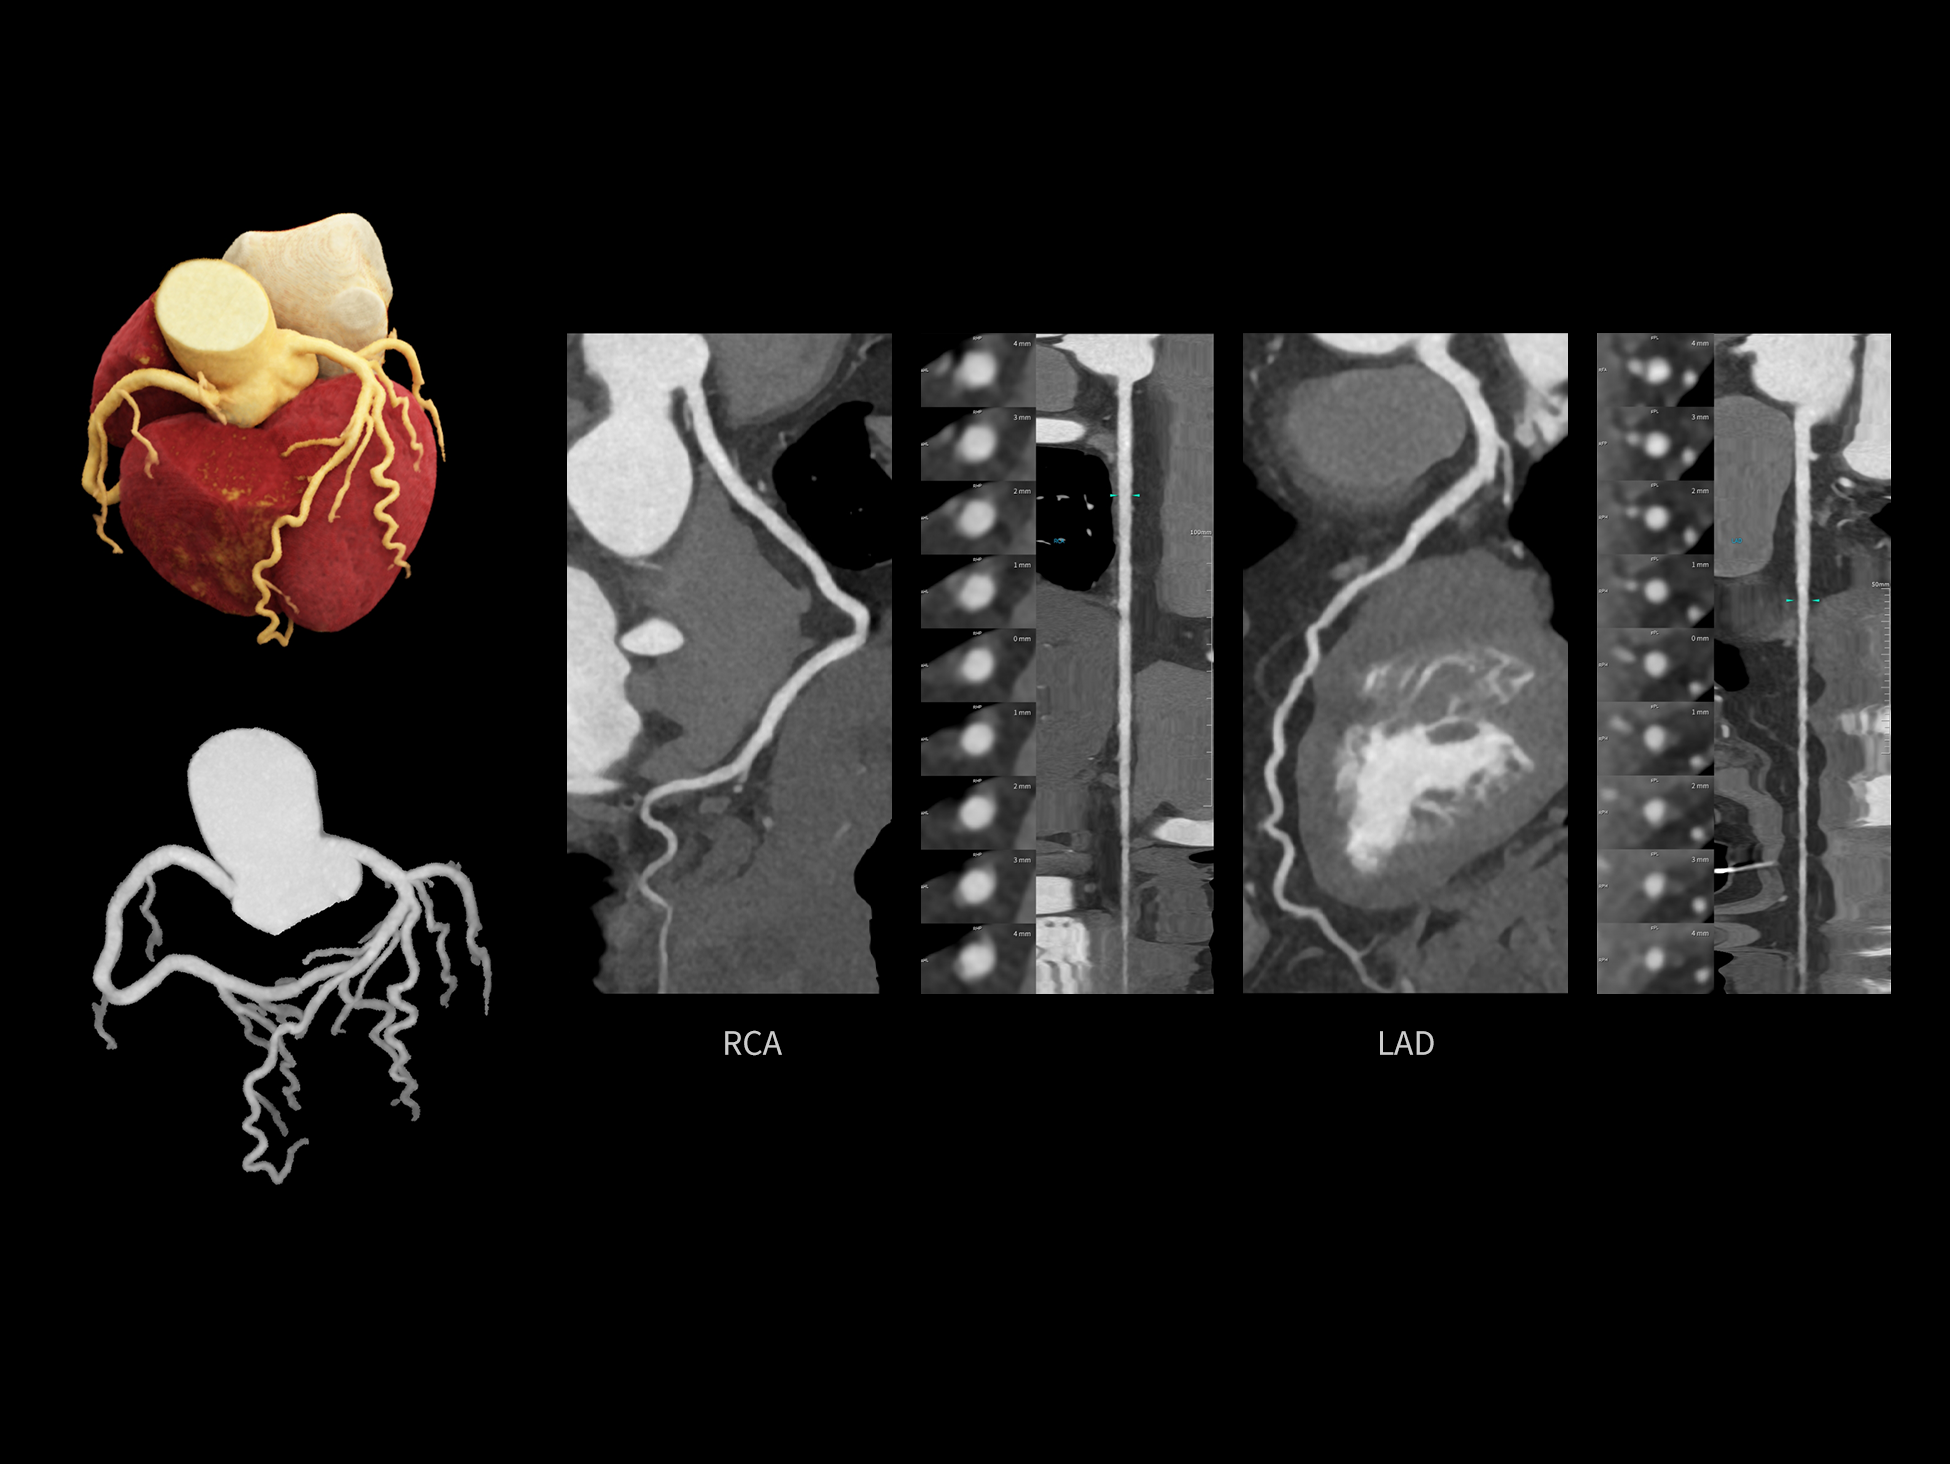

CardioCapture 2.0 通过“识别–追踪–建模–校正”的完整流程,精准分割心脏结构,动态追踪运动轨迹,并构建多时相运动场,最终实现冠脉、瓣膜、心肌及心室结构的同步校正,清晰洞见每一次心跳细微变化,真正将心脏动态掌握于毫秒之间。

CardioCapture 2.0 在目标时相前后重建多时相影像,通过深度学习网络精准提取冠脉中心线,进而建立时相间运动模型,实现对冠脉分段图像的精准运动校正。

冠脉运动校正

全心结构运动校正

CardioCapture 2.0 可对心肌、瓣膜及心室等结构进行同步运动校正。基于深度学习的心脏精细分割,实现了更完整的心脏全局信息提取,能有效抑制全心运动伪影,显著提升心脏细节的清晰度与诊断可靠性。